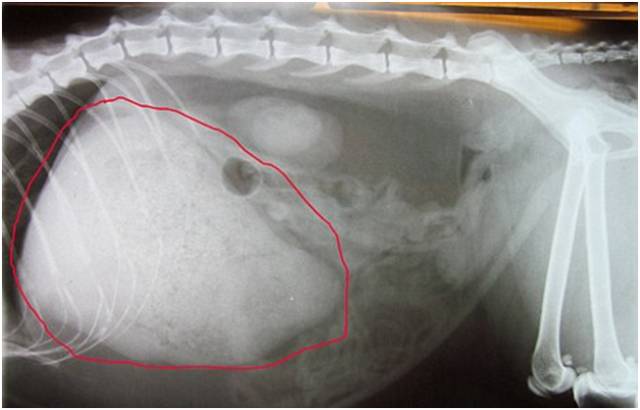

x光看到肚子里全是便便,可怜的猫